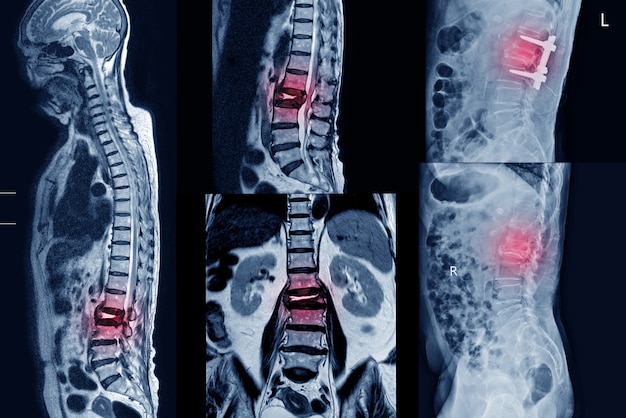

A spine compression fracture occurs when one or more vertebrae in the spine collapse, often due to weakened bones from osteoporosis. These fractures most commonly affect the thoracic spine (upper back) and can lead to pain, loss of height, and spinal deformity if left untreated.

What exactly is a compression fracture? It’s typically defined as a vertebra that has decreased at least 15-20% in height due to fracture. While they can occur anywhere in the spine, compression fractures are most common in the lower thoracic vertebrae (T10-T12) and upper lumbar vertebrae like L1.

Imaging Studies

What imaging techniques are used to confirm a diagnosis of vertebral compression fracture?

- X-rays: Often the first imaging test performed, X-rays can show vertebral collapse and help determine the fracture’s severity.

- CT (Computed Tomography) scan: Provides more detailed images of bone structure and can help identify subtle fractures that may not be visible on X-rays.

- MRI (Magnetic Resonance Imaging): Useful for assessing soft tissue damage, spinal cord involvement, and determining the age of the fracture.

- Bone scan: Can help detect recent fractures and rule out other causes of back pain, such as tumors or infections.

These imaging studies not only confirm the presence of a fracture but also provide crucial information about its location, severity, and potential impact on surrounding structures.

Surgical Intervention

In rare cases, such as severe instability or neurological complications, more extensive surgery may be necessary. This could involve spinal fusion or the placement of hardware to stabilize the spine.

Sometimes surgery is required for spinal compression fractures, no matter the cause. The goal of the surgery is to fuse and repair the fracture, eliminate back pain, and restore posture and ease of movement. The most common surgical procedures for spinal compression fractures are lumbar fusion and vertebroplasty/kyphoplasty.

In a lumbar fusion, the vertebrae are connected with rods.

Minimally invasive lumbar fusion joins the bones of the spine in the lower back together so that there is no longer any motion between them.

This procedure can repair a fracture; correct deformity; and reduce spinal pressure, pain, and nerve damage. Minimally invasive lumbar fusions do not require the large incision or the muscle retraction typically used in conventional fusions. Patients undergoing this procedure have a fast recovery time. A recent advance is the use of a computerized image guidance system for many patients undergoing lumbar fusion. This has the advantage of aiding the surgeon in optimal placement of screws and avoiding injury to delicate nerve tissue.

Until recently, all patients undergoing lumbar fusion required a bone or synthetic graft either from the hip region or from a bone bank. In most patients undergoing lumbar spinal fusion, metal titanium instrumentation is also used. This will typically involve placing pedicle screws into the bone and connecting these with a rod.

Vertebroplasty and Kyphoplasty: Advanced procedures such as kyphoplasty and vertebroplasty allow neurosurgeons to reconstruct compressed vertebral bone, restore alignment, or remove pressure on a nerve.